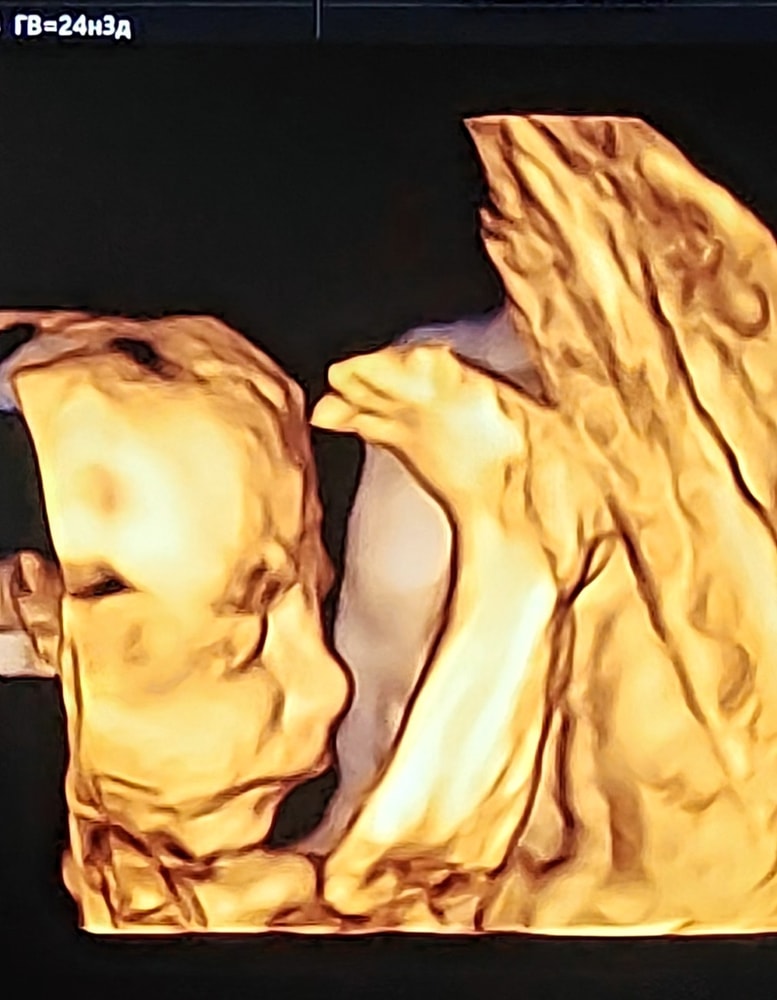

Изображение В нашем случае и до 25 уже можно понять на кого похож)

Олеся, Изображение

Была вчера, ровно 25 было, хорошо видно, только может не показаться или закрыться руками 😅 ходила гулять на второй раз успели заснять без рук 😂

Сходила на УЗИ 3D/4D УЗИ в 25 недель